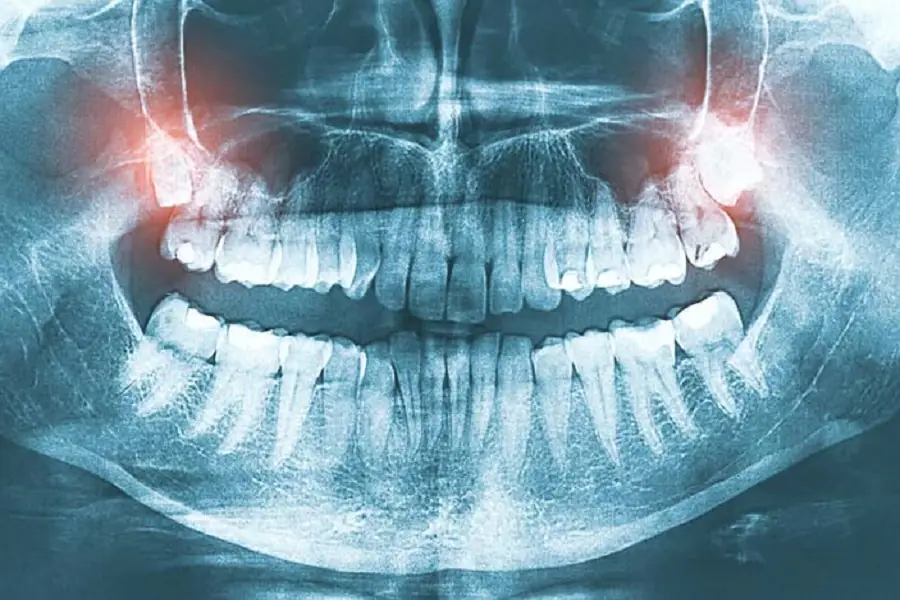

How to treat wisdom tooth pericoronitis

Symptoms are usually local pain, limited mouth opening, etc. General treatment: rinse the blind pocket (gingival pocket) of the crown with a syringe with saline and hydrogen peroxide Apply medicine: iodine glycerin or Palio, periodontal help, etc. 3 to 5 days to reduce inflammation, but Special reminder that the tooth should be extracted in time to prevent the recurrence of inflammation.